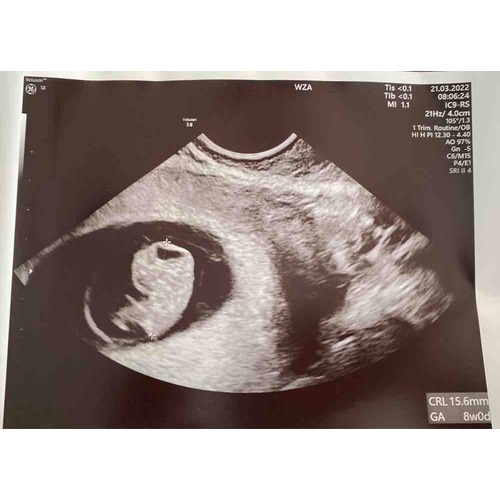

Gefeliciteerd met je zwangerschap! Dit was mijn 8 weken echo.